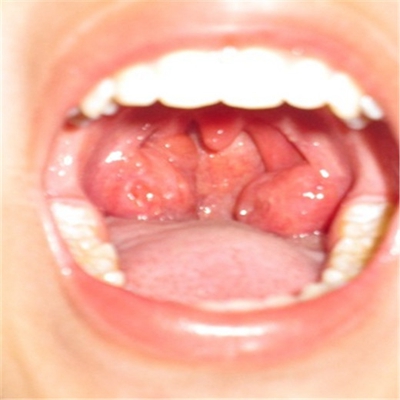

扁桃體惡性腫瘤圖片

扁桃體癌圖 (7)